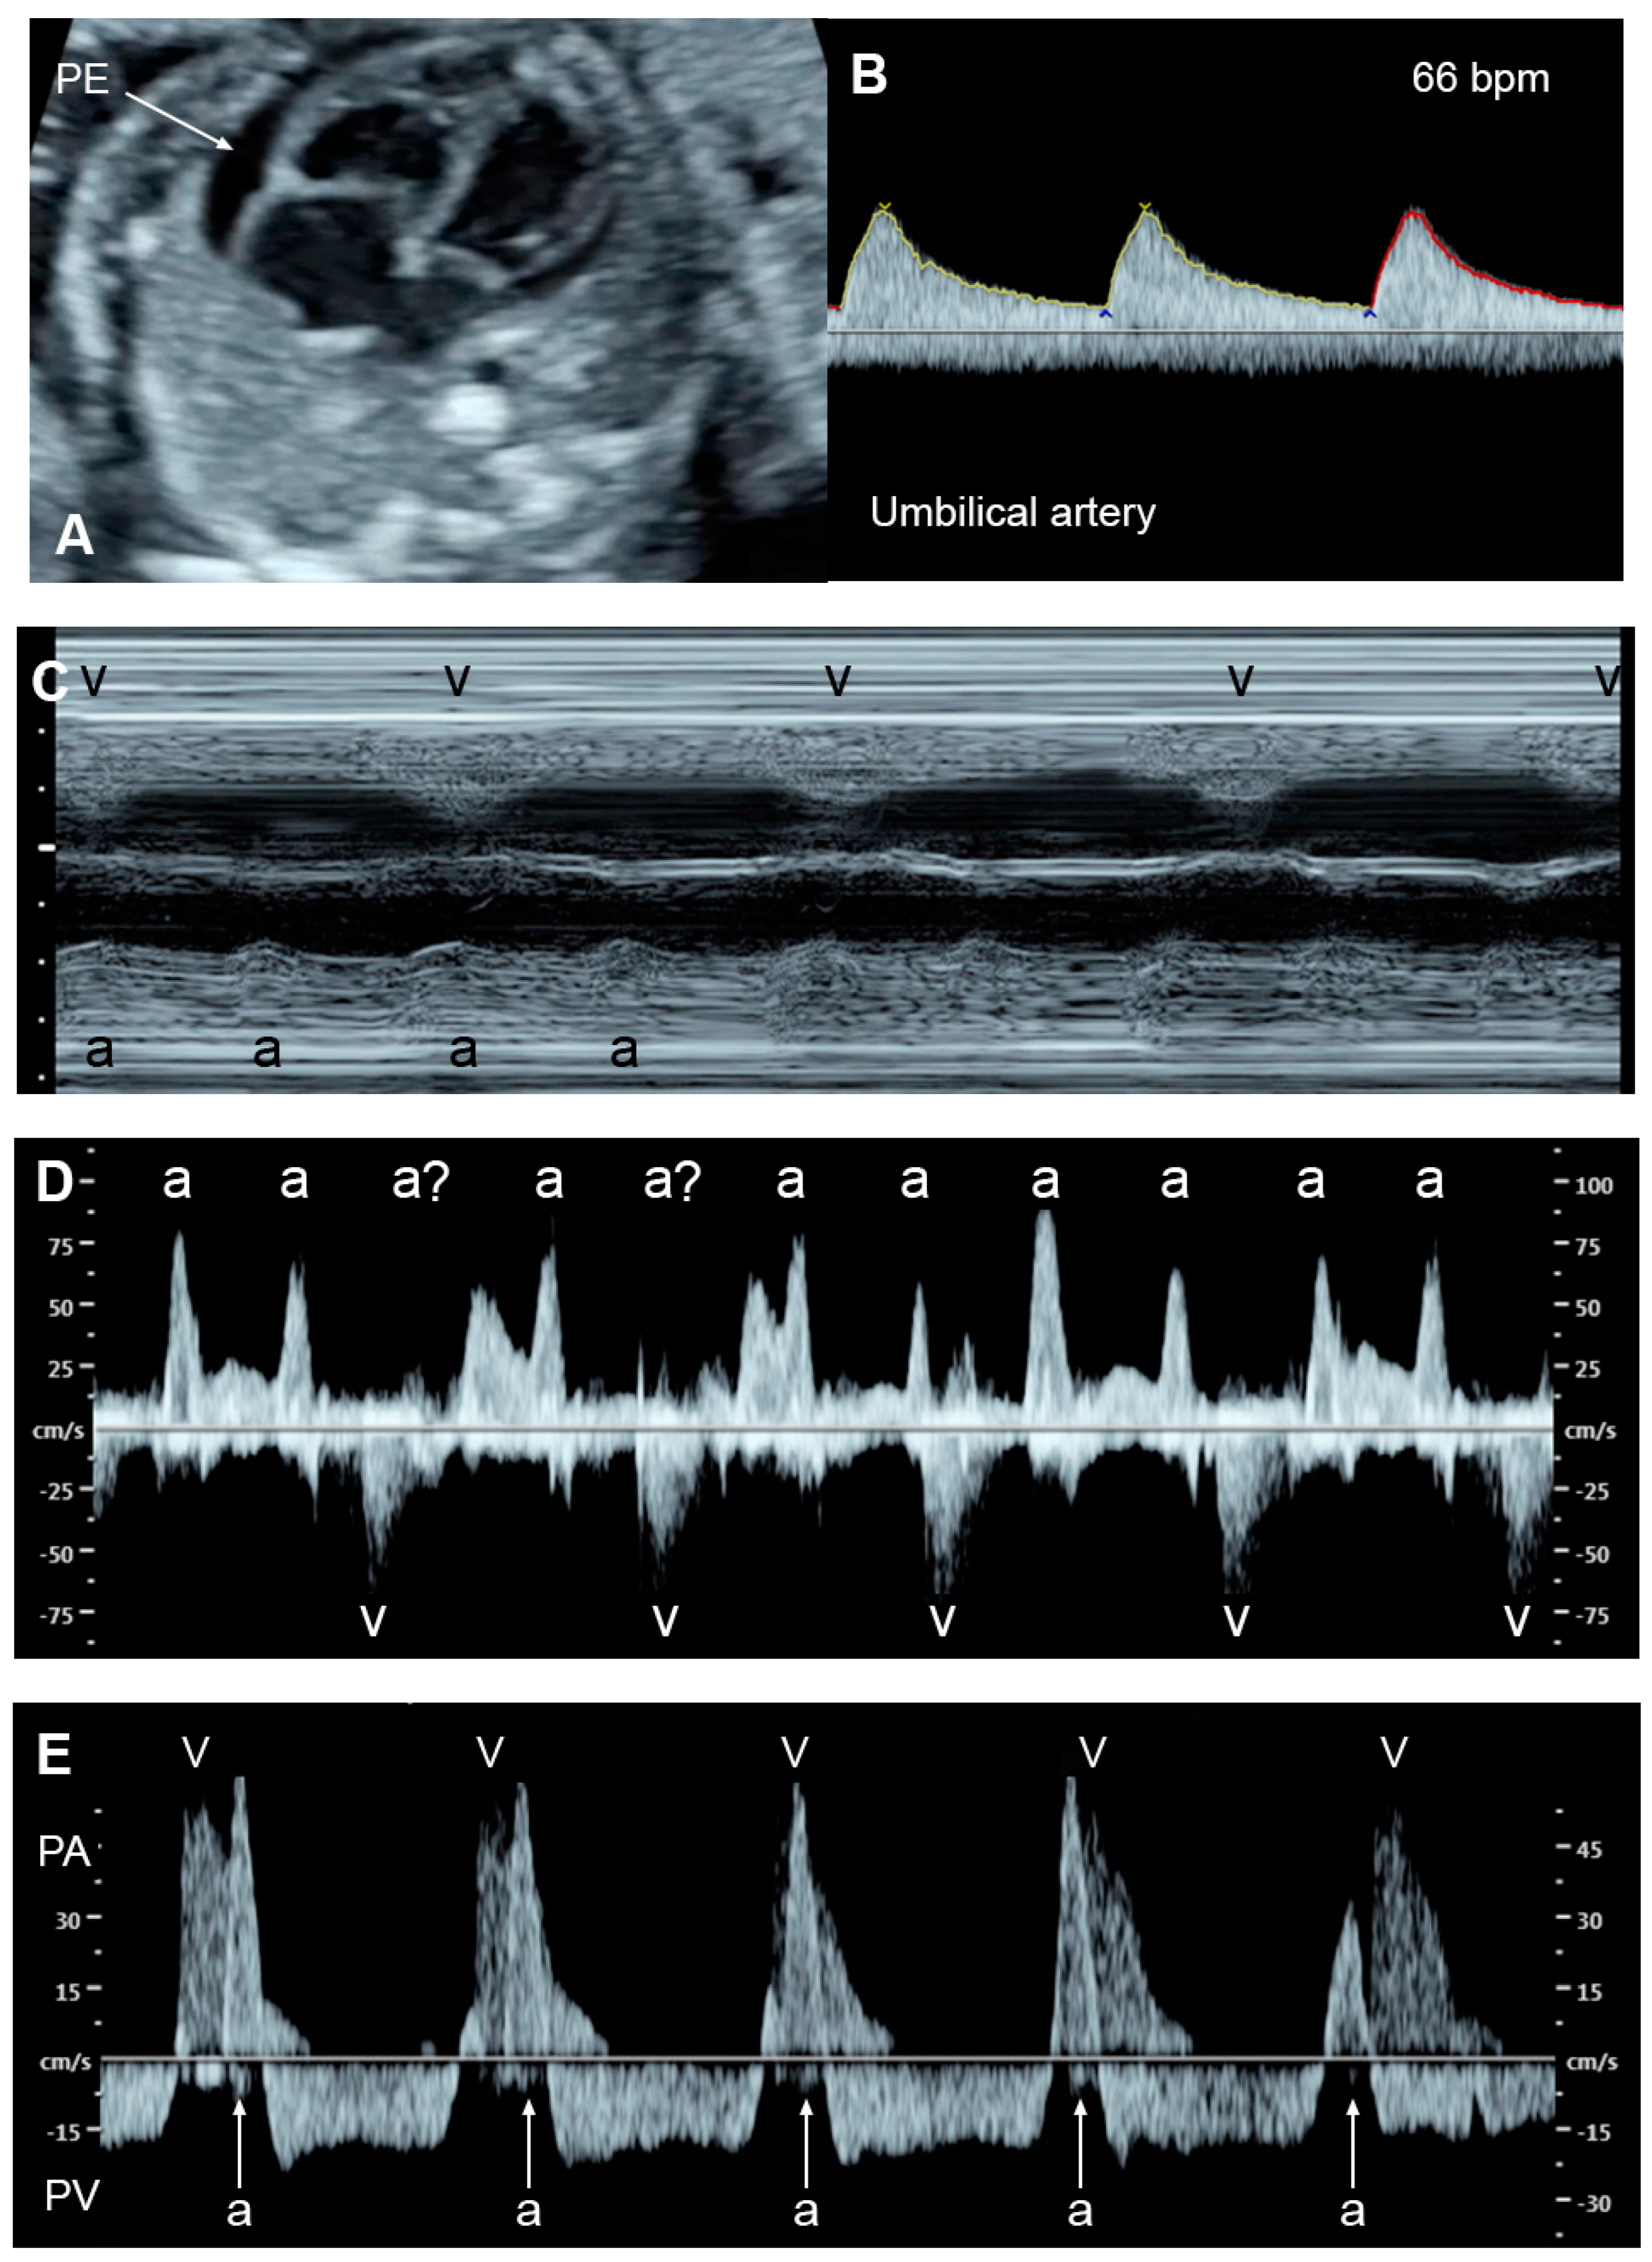

5.1. Fetal Dysrhythmias

- Supraventricular tachycardia and atrial flutter; the most common causes in this group, usually associated with tachycardia of greater than 220 bpm

- AV block with cardiac defects; commonly associated with left atrial isomerism and corrected transposition of the great arteries

- AV block without congenital heart defects, commonly associated with SSA/SSB (Ro/La) antibodies or idiopathic

- Accelerated junctional or ventricular rhythm, relatively rare